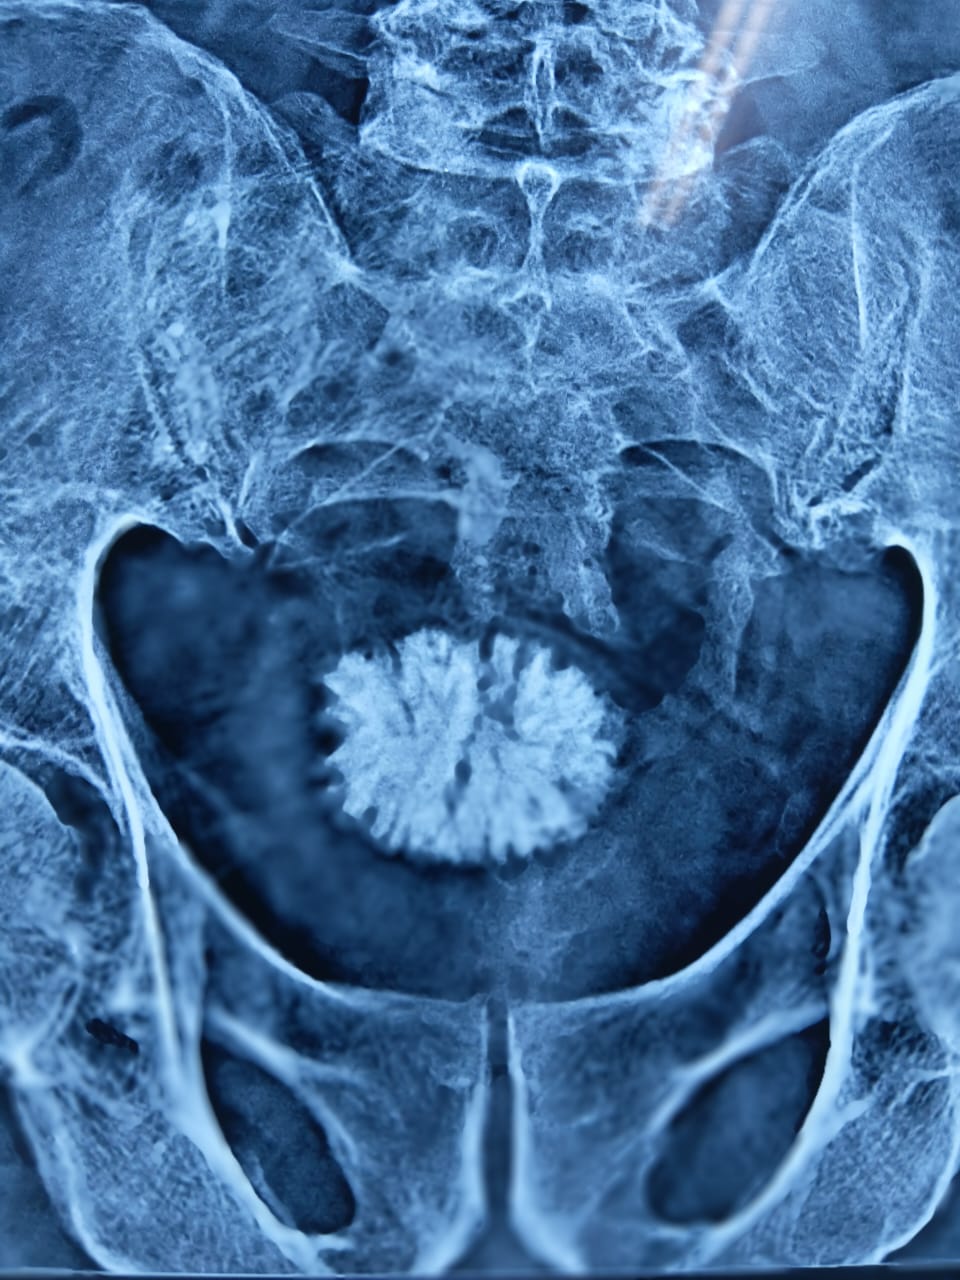

2. Clinical Work at Center